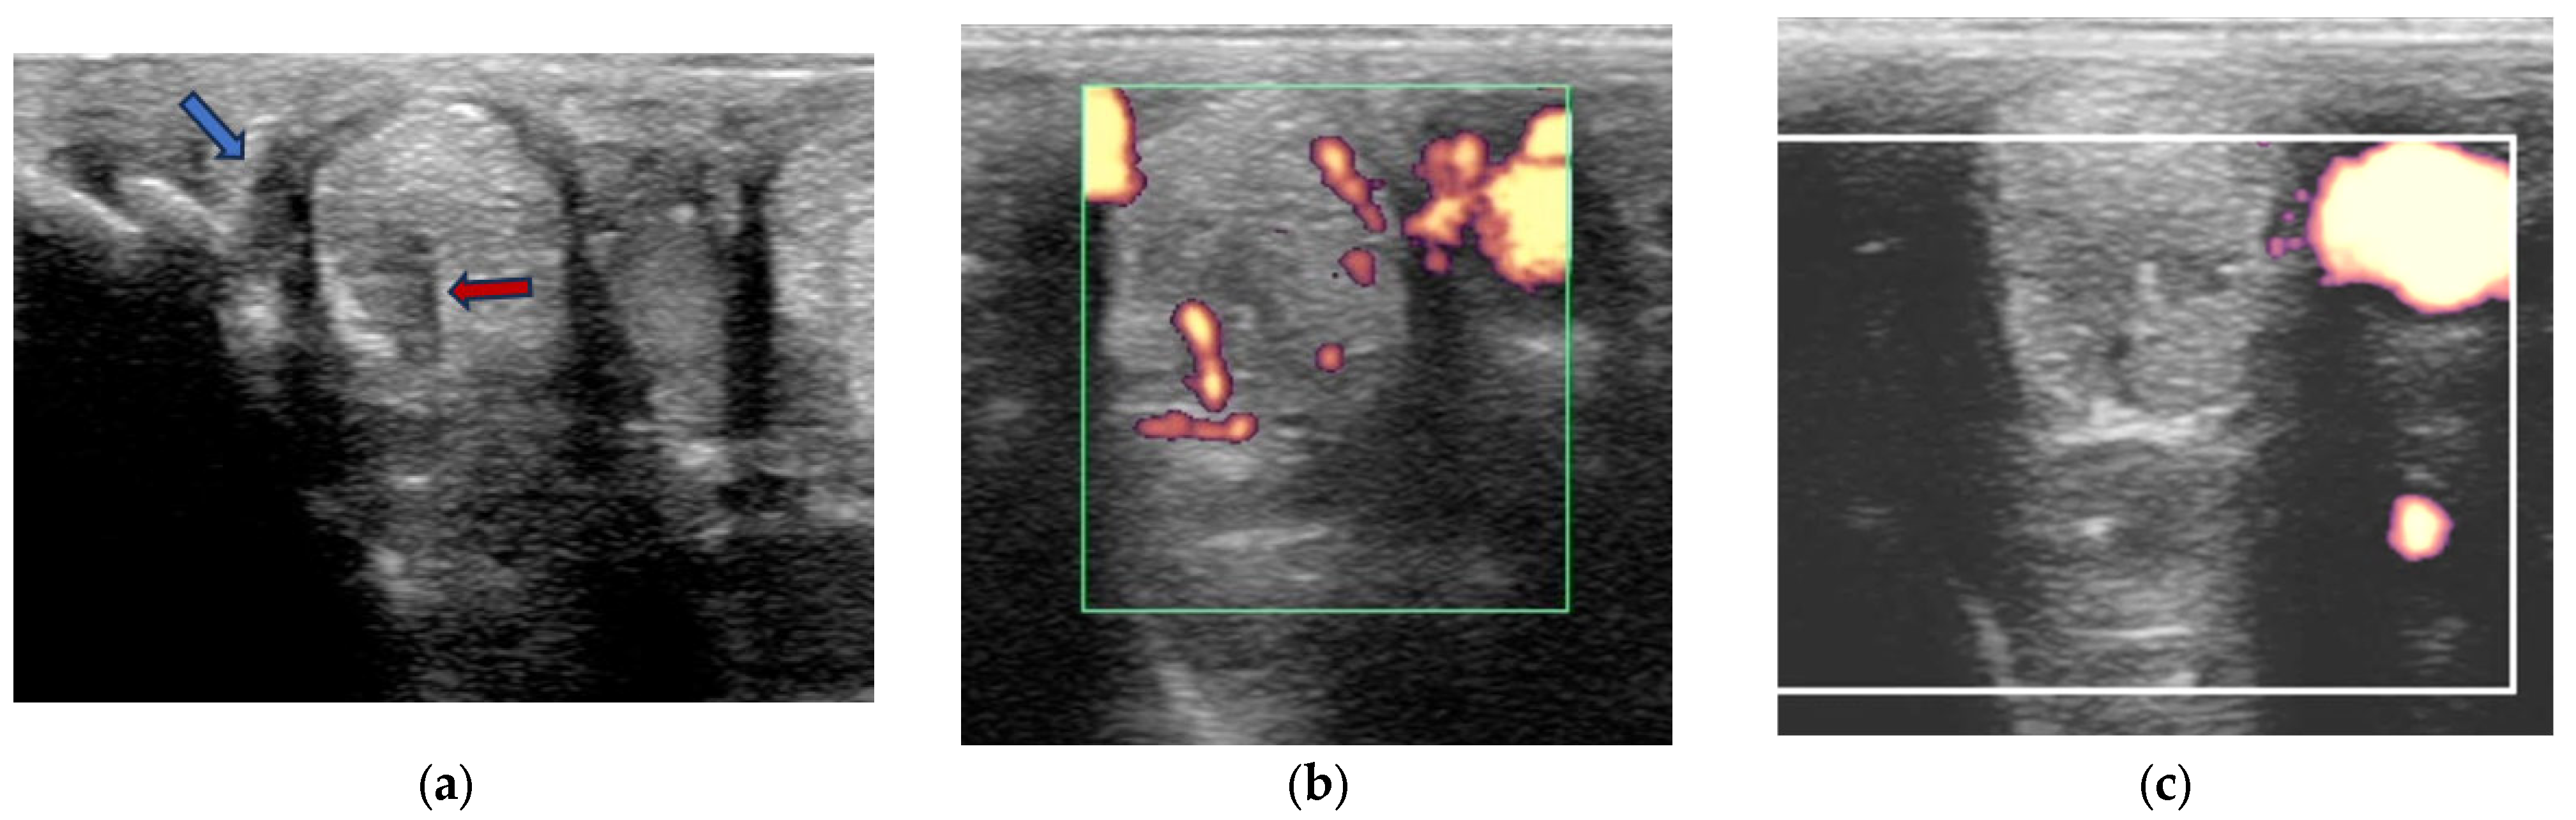

2.3.1. B-Mode Ultrasonography

2.3.2. Power Doppler Examination

- Grade 0 = normal: uniform normal echogenicity; long linear parallel echoes in longitudinal images.

- Grade 1 = mild: less than 25% of the CSA of the ligament was hypoechoic with localised hypoechoic or anechoic lesions. Loss of linear echoes, reduced echogenicity in demarcated areas in longitudinal images.

- Grade 2 = moderate: Hypoechoic or anechoic regions occupying 25–50% of the CSA of the ligament. Loss of long linear parallel echoes in longitudinal images and mild to moderate changes at the enthesis such as irregularity of the bone surface or hyperechoic regions in the SL.

- Grade 3 = severe: Large anechoic and hypoechoic areas occupying >50% of the CSA of the ligament in transverse images. Hypoechoic or anechoic regions in longitudinal images and/or large hyperechoic regions (an avulsion or dystrophic mineralisation) in the SL and/or considerable irregularity of the bone surface at the enthesis.